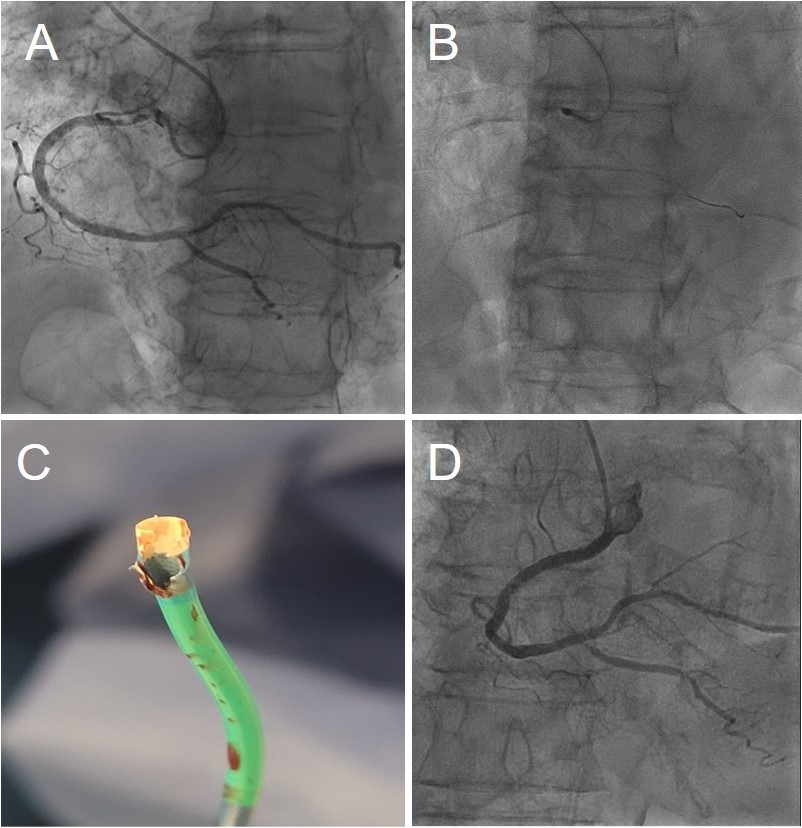

An 85-year-old woman presented with a subocclusive (99%), severely calcified ostial lesion of the right coronary artery (RCA) (Figure A, Video 1). A 6F Launcher Amplatz Left (AL) 0.75 guide catheter (Medtronic) (inner diameter: 1.80 mm/0.071 in) was selected to maximize back-up support. After wire exchange for a RotaWire (Boston Scientific) using a 1.9F Caravel microcatheter (ASAHI INTECC), rotational atherectomy (RA) was initiated with a 1.75-mm burr. Although standard best practice is to initiate RA with a 1.5-mm burr to minimize the risk of burr entrapment and allow stepwise lesion reassessment,1 a 1.75-mm burr was selected upfront in this case to achieve a burr-to-artery ratio closer to 0.5, aiming for optimal plaque modification in a large-caliber vessel (approximately 4.5 mm).

Given the severity of the ostial lesion and immediate resistance at the coronary inlet, RA was initiated close to the distal tip of the guide catheter, requiring a careful millimeter-by-millimeter advancement with multiple short runs (total cumulative burr time: 75 seconds). After these initial incremental passes, a final run was performed, as illustrated in Video 2. Following atherectomy, intravascular lithotripsy (IVL) could have been considered as part of a rota-lithotripsy strategy; however, a “Rota-Cut” approach was favored, as the prolonged balloon inflations required for IVL might be poorly tolerated in a very dominant RCA. Shorter inflation with a cutting balloon were therefore preferred to maintain hemodynamic stability, while also offering a more cost-effective approach. The lesion was then further prepared using a 3.5 × 10-mm Wolverine cutting balloon (Boston Scientific) with a single inflation at a maximum pressure of 16 atm for a total duration of 20 seconds. A double-wire technique—1 wire positioned in the ascending aorta for stability and 1 in the RCA—was subsequently used to deliver and accurately position a 4.0 by 24-mm Synergy Megatron stent (Boston Scientific) (Video 3).

The complication remained clinically silent until the end of the procedure, when unexpected resistance was encountered during stent balloon retrieval. Withdrawal of the system revealed catastrophic structural damage of the guide catheter tip (Figure C); the polymer soft tip of the Launcher was extensively machined and charred, with complete exposure of the internal stainless-steel braiding. Final angiography after high-pressure optimization to 4.60 mm showed an excellent result with Thrombolysis in Myocardial Infarction-3 flow (Figure D, Video 4). At the 8-month clinical follow-up, the patient remained asymptomatic.

- Shape constraint: Aggressive guide shapes such as the AL induce distal curvature and eccentric alignment (Figure B, Video 2), effectively abolishing the minimal clearance and allowing the high-speed burr to behave like an industrial lathe against the catheter wall.